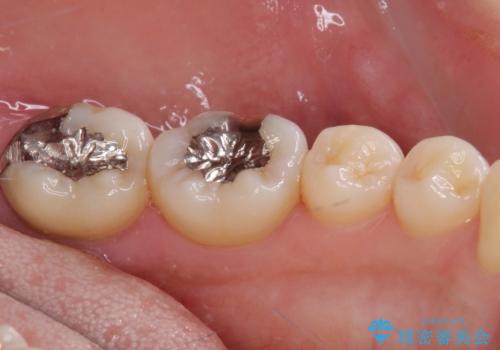

奥歯が痛い 保険治療後に症状が発現した歯のむし歯治療

- 近医にてむし歯治療を行った後に痛みが出たとのことで来院された患者様です。

左下奥歯は術後から咬合時の痛みが発現し、来院時には脈を打つような痛みが認められました。

診察の結果、神経を取り除く必要があると判断されたため根管治療を行いました。

その後、左上の奥歯にも咬合時の痛みが認められ、レントゲン写真より歯内の神経が失活していることが分かりました。

2歯ともに根管治療を行い、その後はオールセラミッククラウンにて補綴治療を行うこととしました。

来院時には食事が取れないほどの痛みを訴えていらっしゃいましたが、処置後からは痛みが軽減され、食事もいつも通りに取れるようになりました。